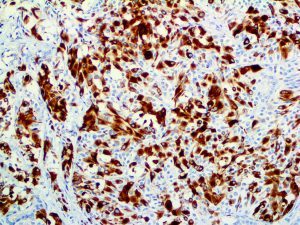

It is the ICU physician who is most likely to witness one of the deadliest manifestations of the abnormal immunological response, the cytokine storm syndrome (CSS). This response is also referred to by some as the cytokine release syndrome (CRS). CSS is characterized by continuous activation and expansion of macrophage and lymphocyte populations, which secrete large amounts of cytokines, causing the cytokine storm. This massive cytokine release is akin to hemophagocytic lymphohistiocytosis (HLH) disease, a syndrome characterized by initial unchecked and persistent activation of cytotoxic T lymphocytes and NK cells.

Clinical and laboratory manifestations of HLH include fever, enlarged liver and/or spleen, neurologic dysfunction, coagulopathy, liver dysfunction, cytopenias (i.e., low levels of erythrocytes, leukocytes, and/or platelets), hypertriglyceridemia, hyperferritinemia, hemophagocytosis, and eventually diminished NK cell activity as the immune system becomes progressively paralyzed. HLH can be familial (primary HLH) or secondary to another disease process (sHLH), such as rheumatic disease, in which it is referred to as macrophage activation syndrome (MAS, characterized by elevated ferritin).